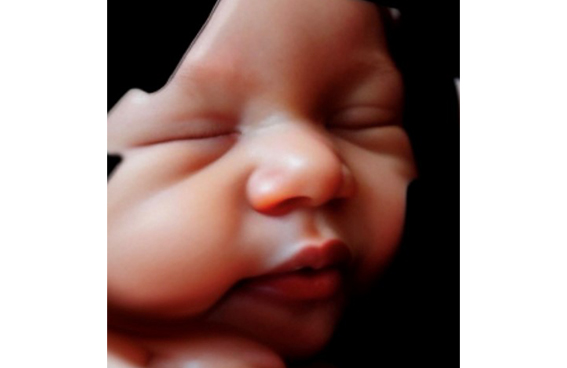

Se puede realizar en cualquier momento de la gestación aunque preferimos realizarla a partir de la semana 28 porque por la madurez fetal realiza más gestos como sacar la lengua, reír, bostezar , etc y además con la incorporación de la Inteligencia Artificial a la ecografía 5D esta se convierte en una imagen hiperrealista , es como será tu bebé cuando nazca.